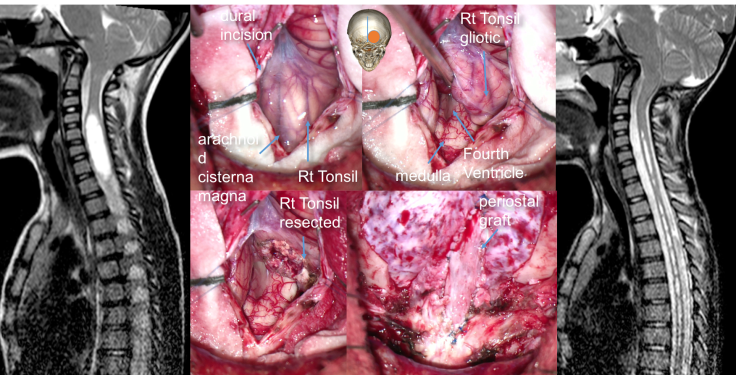

la décompression de la charnière craniocervicale

c’est l’intervention de référence. la technique varie suivant les équipes, le but est d’obtenir une bonne décompression de la moelle allongée (bulbe) et une circulation libre du liquide cérébro-spinal.

le rationnel de la chirurgie et la technique opératoire sont détaillés sur la page technique Chiari